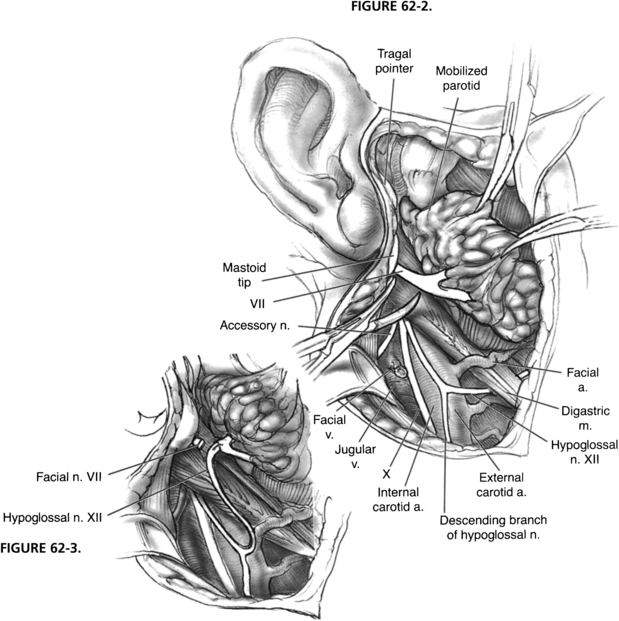

(PDF) Hypoglossal-Facial Nerve Anastomosis in Facial Reanimation: A …

Anatomic locations of hypoglossal nerve injury: (A) Nerve compression …

Figure 1 from Comparison of Direct Side-to-End and End-to-End …

Analysis of Preoperative Factors Influencing Hypoglossal-facial ‘Side …

Figure 3 from Hypoglossal-facial-jump-anastomosis without an …

Hypoglossal Facial Anastomosis | Ento Key